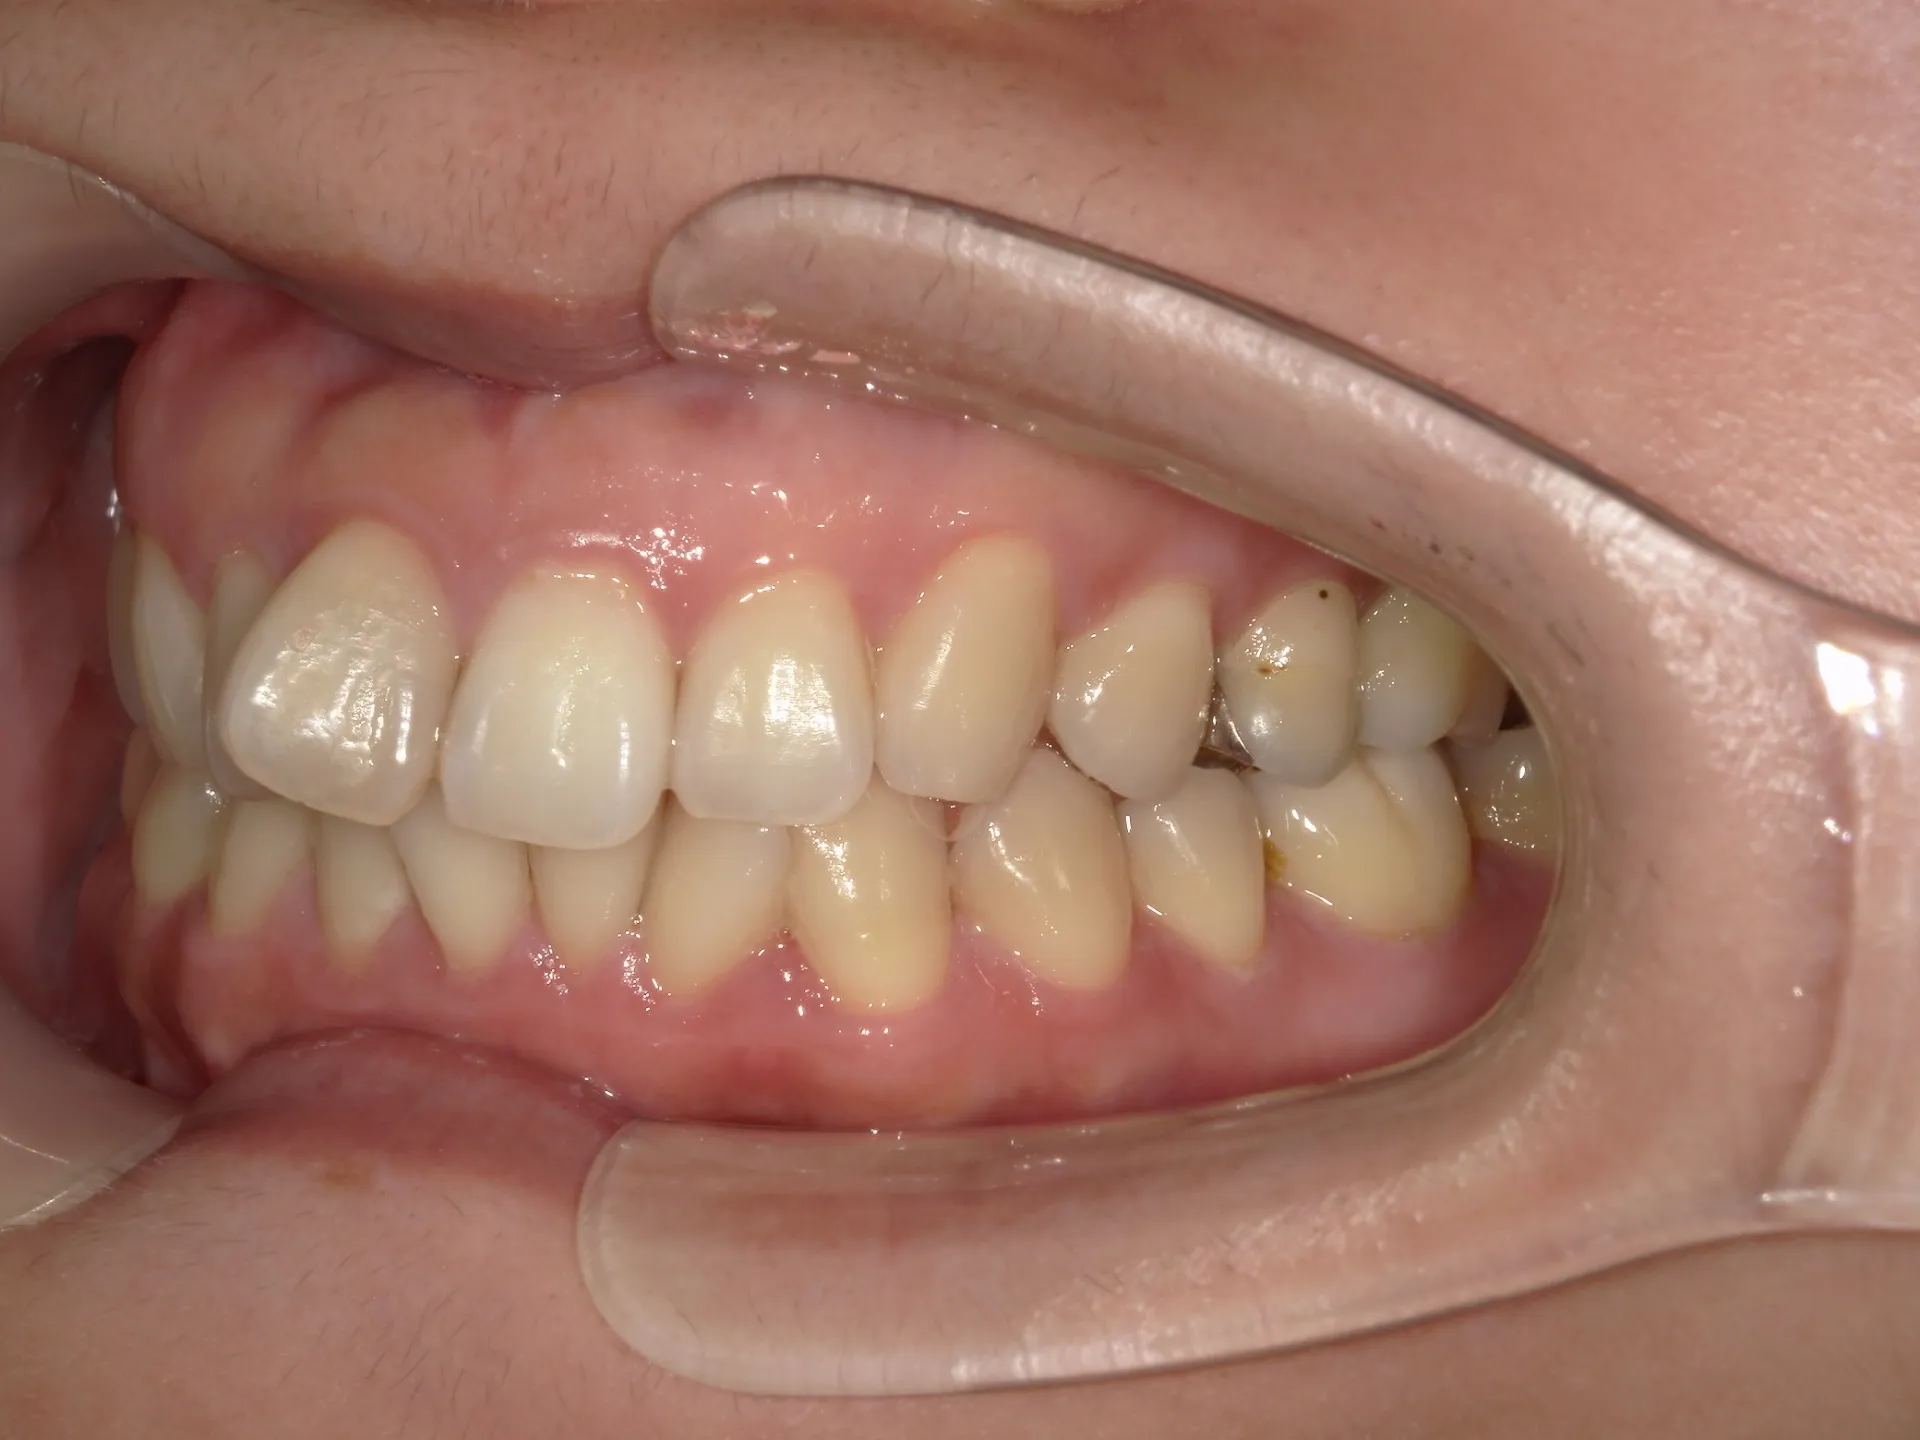

上の前歯が1本大きくねじれ、更にその歯に変色も見られました。

歯のねじれと歯の色を同時に治す方法として、セラミックの被せものがあります。

セラミックの被せを入れて歯の形や色、位置も治すことができますが、今回の状態で1本分のセラミックの被せを入れるとかなり細くなる被せを入れなければなりません。なぜかと言うと歯がねじれている原因は歯が真っ直ぐ生えるスペースがなかったことです。ここに無理やり被せで治そうとすると通常の歯の約半分程度の幅の被せになってしまいます。

そのため今回は通常の矯正治療とその後にご自身の歯を利用してウォーキングブリーチを行いました。

セラミックの被せ一本で治せた方が、費用感や治療期間は少なくできますが、仕上がりを考えるとやはり今回のようなケースでは、矯正治療とホワイトニングを併用した方が良い選択であったと考えられます。